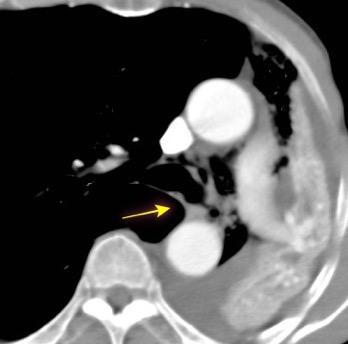

149. TORACOABDOMINAL: GANGLIOS

150. TORACOABDOMINAL: S SEUDOQUISTE PANCREÁTICO